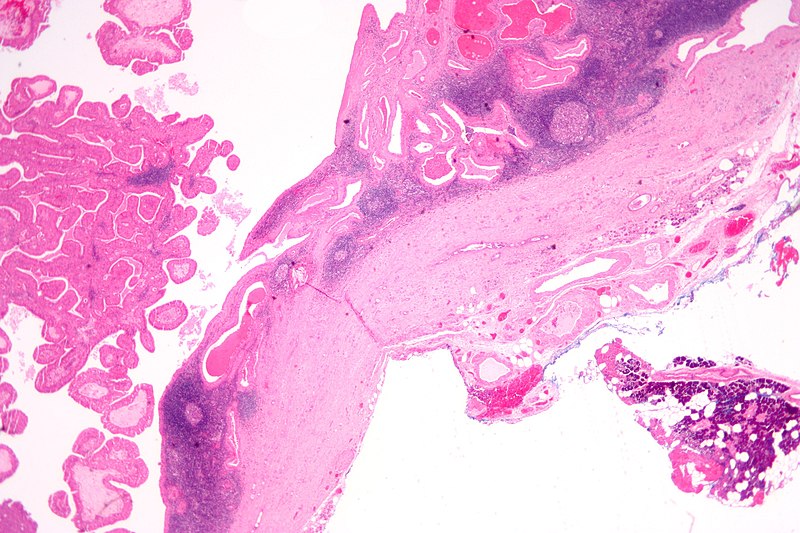

Pleomorphic Adenoma

Pleomorphic adenoma is a benign tumor made up of both epithelial and stromal tissue.

Pleomorphic adenoma is the most common salivary gland tumor.

Pleomorphic adenoma appears as a moving, painless mass that is constrained to the angle of the jaw.

Histologically pleomorphic adenomas have a myxoid component and a stromal component.

Pleomorphic adenoma is associated with the PLAG1 gene mutation.

Treatment of pleomorphic adenoma is surgical resection.

Small islands of tumor that extend through the tumor capsule frequently result in an incomplete resection.

There is a high recurrence rate for excised pleomorphic adenomas.

Rarely the benign pleomorphic adenomas may develop into their malignant counterparts carcinoma-ex pleomorphic.